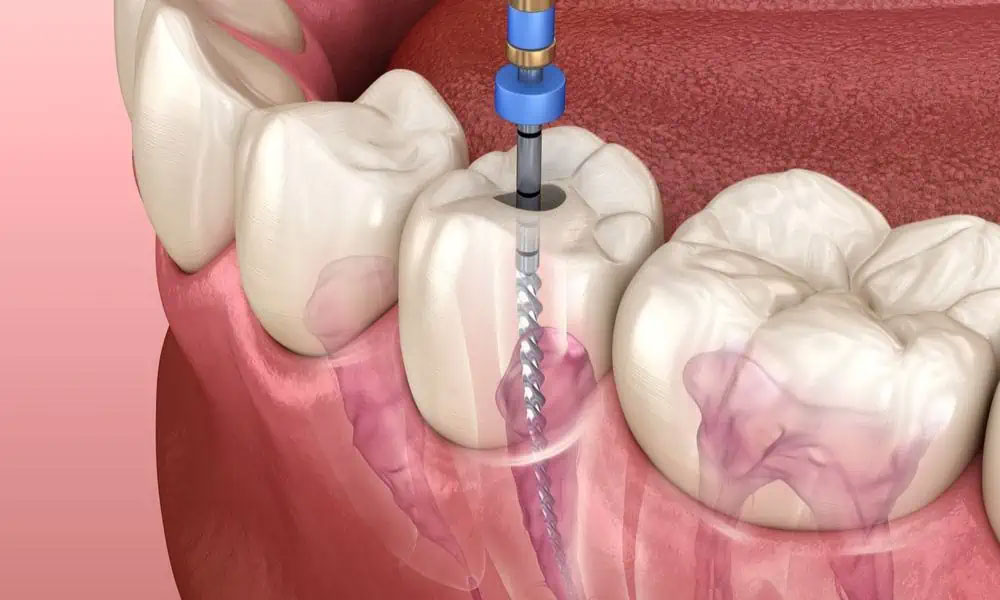

Root canal

A root canal is a dental procedure used to treat infection or damage within the pulp of a tooth. The pulp contains nerves, blood vessels, and connective tissue, and when it becomes inflamed or infected due to deep decay, trauma, or cracks, a root canal is performed to save the tooth.